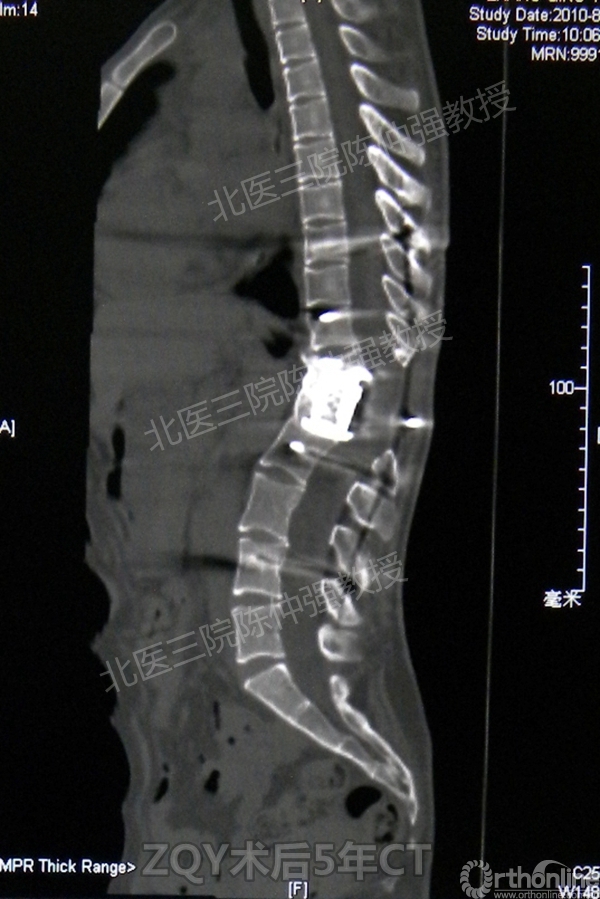

ZQY术后5年

患者女性17岁,胸腰椎陈旧结核性侧后凸畸形,局部呈“麻花状”扭转,无神经功能受损表现。2005年,陈仲强教授带领团队实施后路+侧前方联合入路脊柱节段切除、双轴旋转矫形术。术后患者外观显著改善,神经功能正常。术后随访证实患者截骨矫形节段骨性融合良好,矫形效果持续良好。